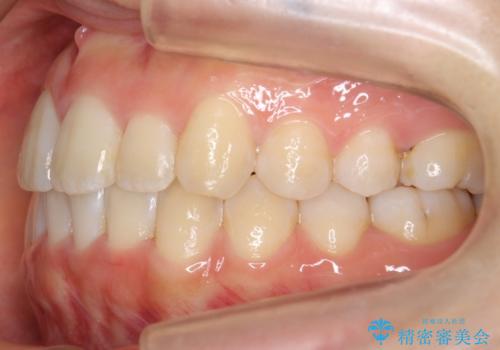

上下の前歯のがたつき 歯を抜かずに矯正

- 上下の前歯のがたつきを主訴に来院。

歯を抜かずに前歯を揃えています。

奥歯を後ろに下げたりなどはしていません。

奥歯を外に広げ、前歯中心に歯を少し削っていますが、健康には問題ない範囲で行なっています。